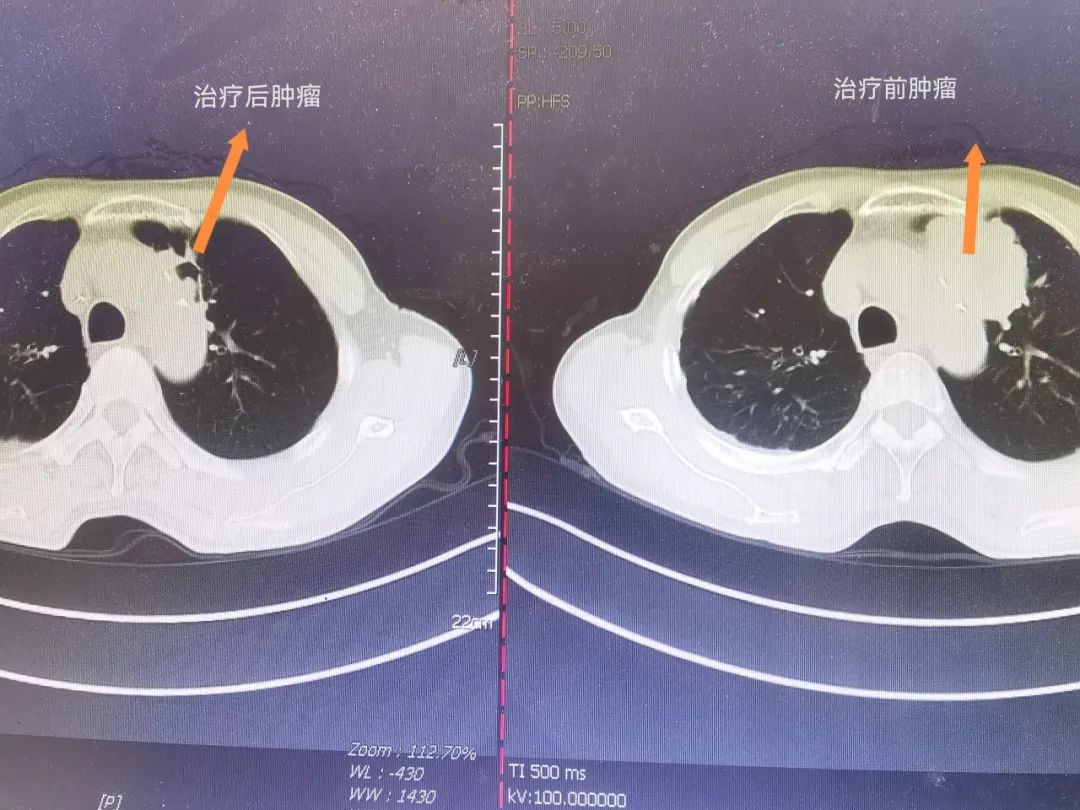

此次,曾劍主任開展了2臺標(biāo)準(zhǔn)的左上肺癌根治術(shù)手術(shù)教學(xué),其中一臺手術(shù)的患者是化療加免疫治療2周期后腫瘤由近6cm縮小至約2cm且已空泡狀,淋巴結(jié)亦有所消退。盡管該患者的腫瘤消退明顯,但此類免疫治療后的縱隔淋巴結(jié)及肺門結(jié)構(gòu)難以辨別,且質(zhì)地硬、難以分離,加之患者均為多發(fā)鈣化的門釘淋巴結(jié),血管、神經(jīng)被完全包繞其間,因此手術(shù)難度只增不減,在業(yè)界中普遍認(rèn)為術(shù)中難度大、風(fēng)險(xiǎn)高。